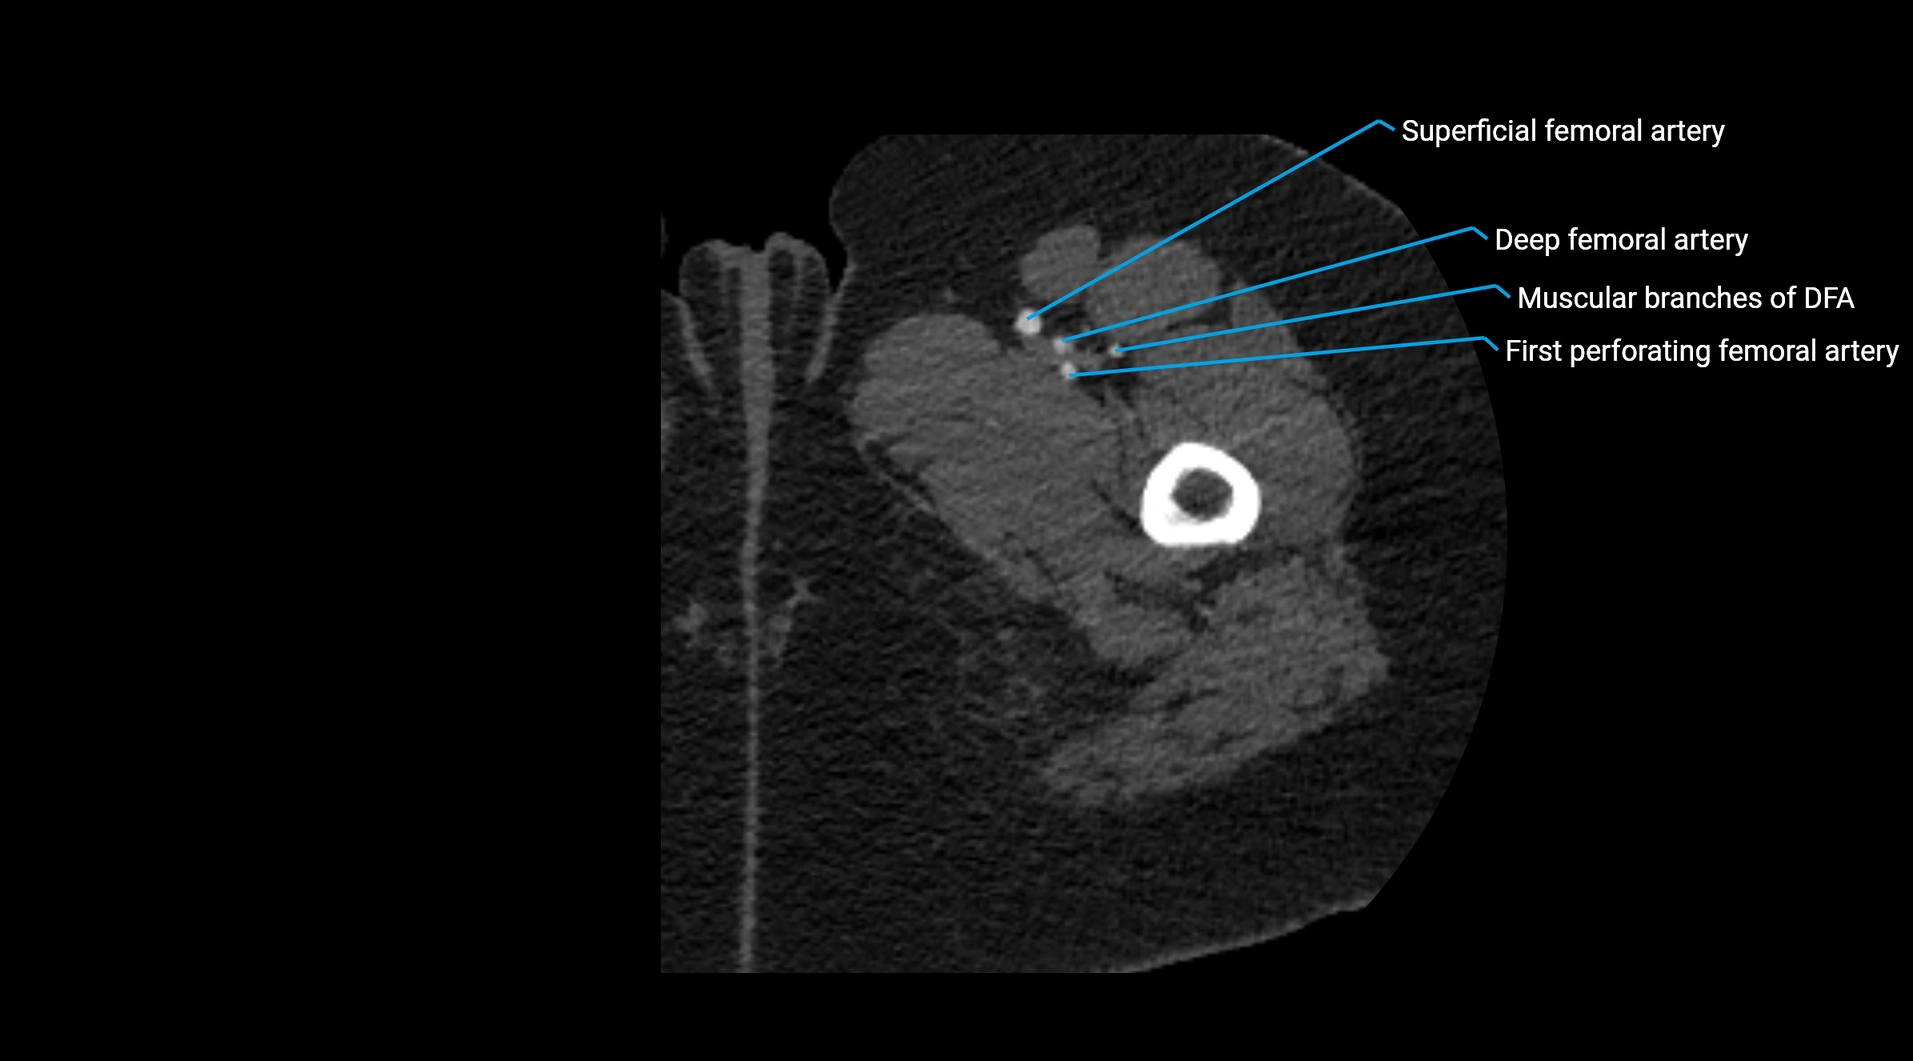

Contrast-enhanced CT (CTA):

• Gold standard for abdominal aortic imaging

• Provides excellent detail of lumen, wall, aneurysm, thrombus, and branch vessels

• Multiplanar and 3D reconstructions help in aneurysm measurement, stent graft planning, and dissection evaluation